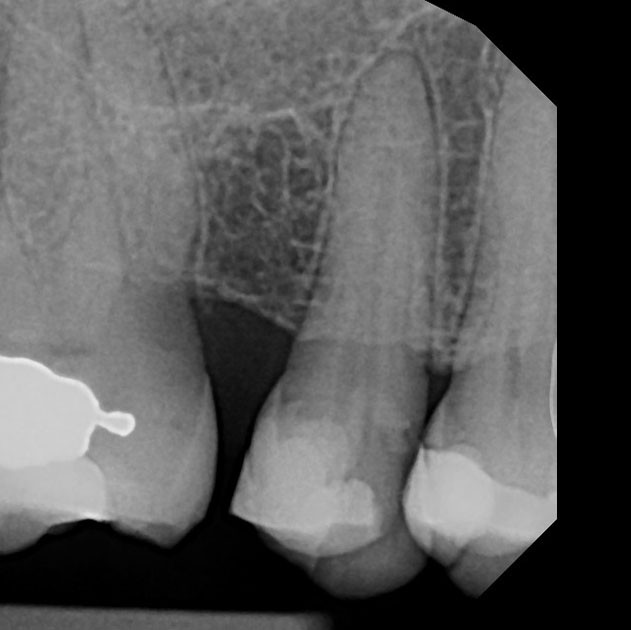

RCT